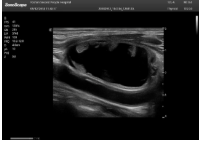

2相控陣探頭

探頭面是平面,接觸面小,近場視野最小,遠(yuǎn)場視野大,成像視野呈扇形,適用于心臟。

肥厚性心肌病-心尖四腔